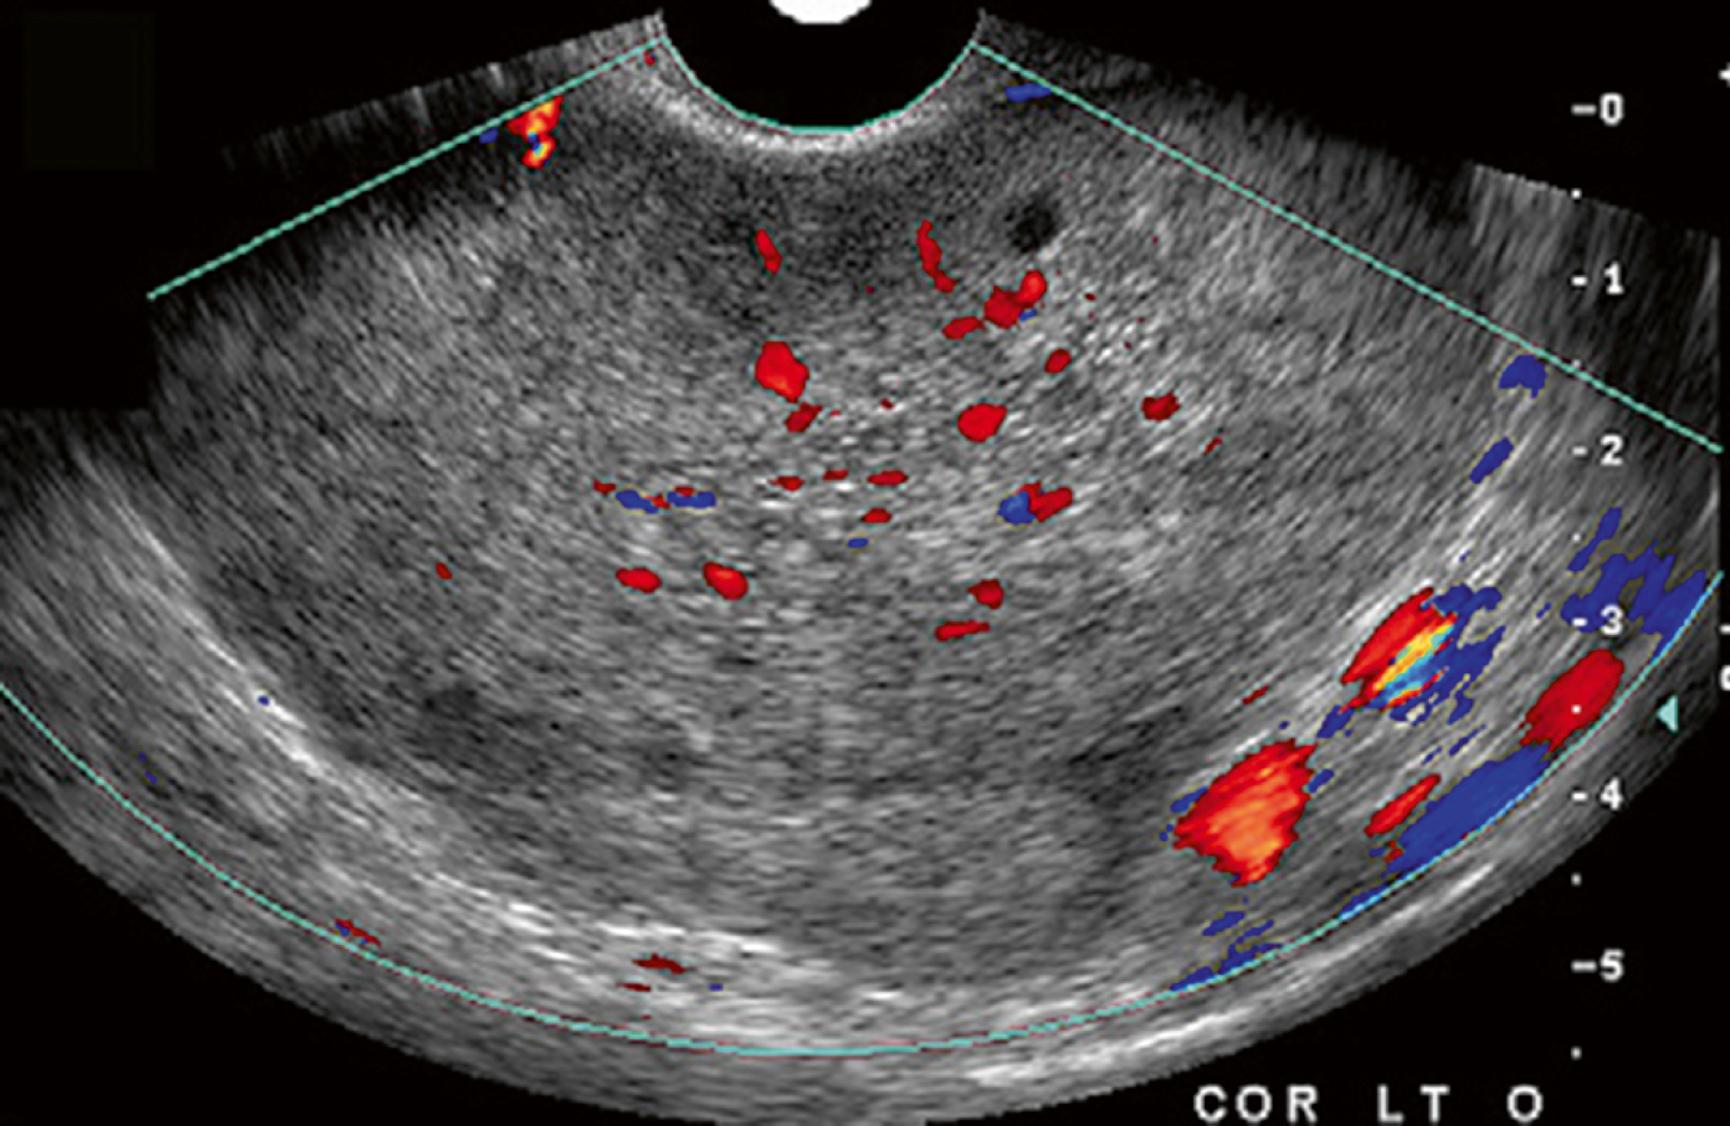

Doppler ultrasound findings are inconsistent in the definitive diagnosis of adnexal torsion. Up to 60% of surgically proven cases have ovarian blood flow on the preceding Doppler examination ( Fig. 86.3 ). These findings may vary depending on the time of the examination because torsion may occur intermittently, and clinical symptoms commonly precede arterial compromise. If a large adnexal mass is present, the examination may also be technically difficult to perform. Despite these limitations, the Doppler examination is still useful, as recognition of ovarian enlargement or masses, as well as detection of abnormal venous flow is particularly important in early cases of torsion ( Fig. 86.4 ). Absence of arterial flow is highly specific for torsion, with a positive predictive value nearing 100%. Visualization of the twisting of the pedicle and coiled vessels is referred to as a “whirlpool sign” and has a 90% positive predictive value for torsion.

Fig. 86.3, Ovarian torsion with color Doppler image demonstrating venous and arterial flow.